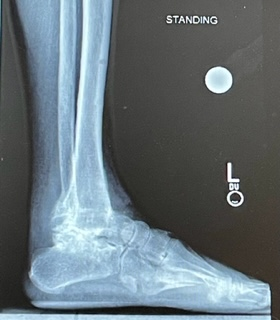

When the fixator was removed, I had to wear a cast for several weeks and then a boot for another pair of weeks. My mood and outlook began to change. My ankle and foot felt strong, straight, and flat! After the removal of the boot, my wife and I went to diner to celebrate! I haven’t felt as confident in a long, long time! I do not have any pain. I am so very happy with the correction and greatly improved quality of life that Dr. Rozbruch has given me. It was so much fun to mow the lawn and work in the garden again!

My left foot is now like my right for the first time in my life! I can even run for the first time in years!